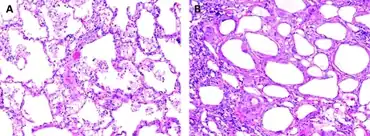

The gross appearance of a lipid pneumonia is that in which there is an ill-defined, pale yellow area on the lung. This yellow appearance explains the colloquial term "golden" pneumonia.

At the microscopic scale foamy macrophages and giant cells are seen in the airways, and the inflammatory response is visible in the parenchyma.